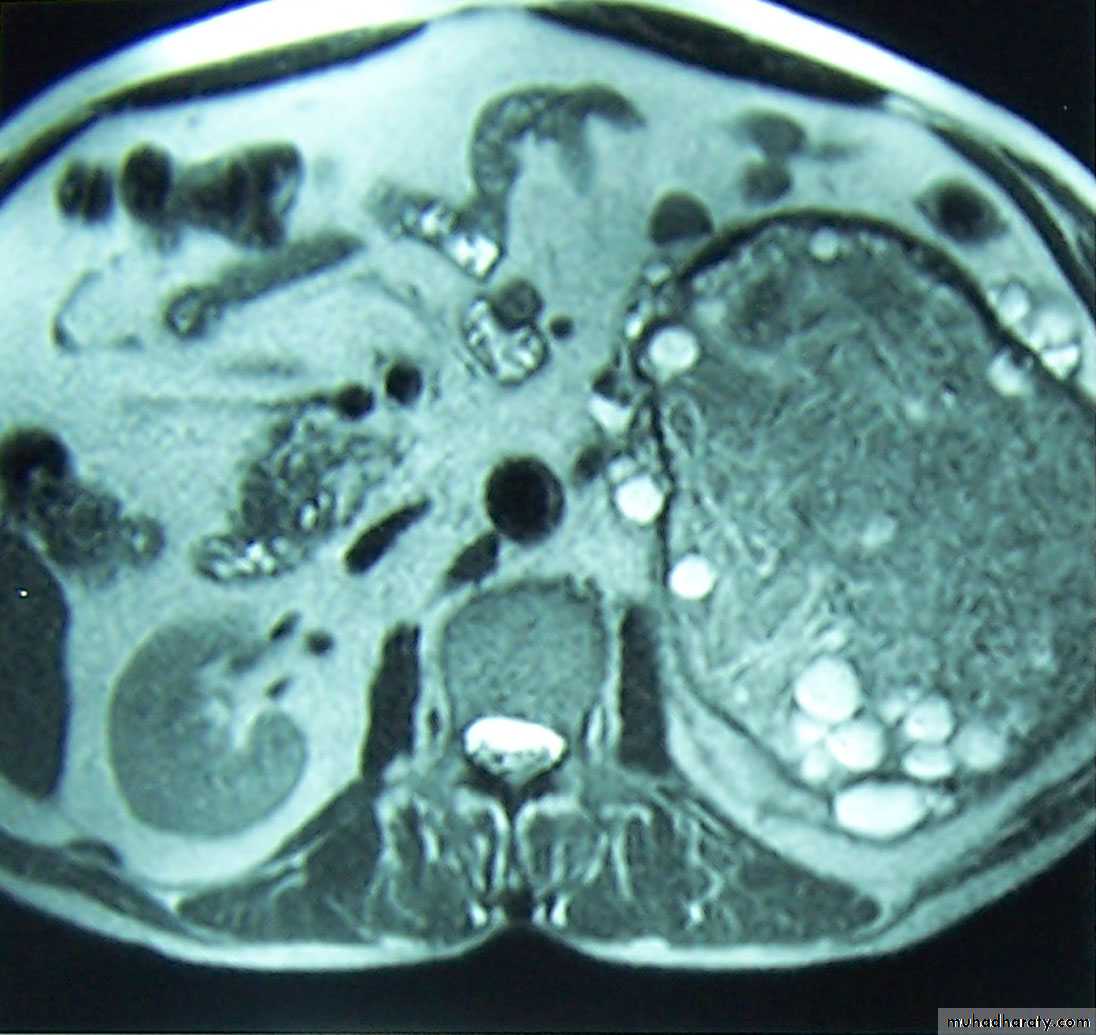

What's the imaging modalityWhat's the diagnosisCT with and without contrast >>> Rt. kidney cancer(RCC)